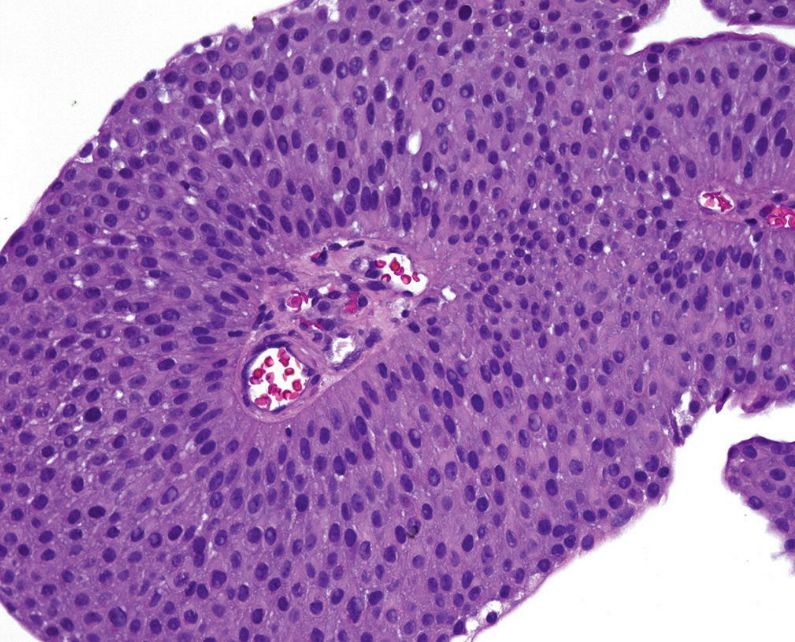

Urothelial papilloma

Note that the urothelium resembles normal urotheium both in thickness and in cytology. Some large umbrella cells are visible.

Sometimes the normal urothelium can look wavy or tufty, so make sure that there is a true fibrovascular core before calling a papilloma.